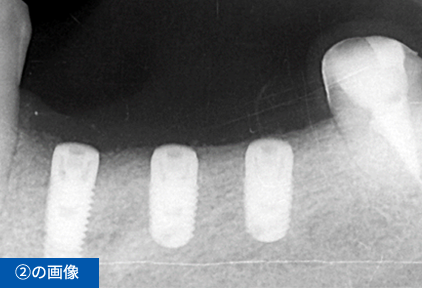

左下④56⑦番のブリッジの脱離にて来院(④⑦はブリッジの支台歯56は欠損)

| 治療期間・通院回数 | 10カ月・10回(消毒のみも含む) |

| 費用 ※保険外診療 | 総額1,485,000円(税込) インプラント3本、手術2回、CGF、遊離歯肉移植、CT撮影、被せ物の型取り(印象)、被せ物(フルジルコニア)3本、投薬 |